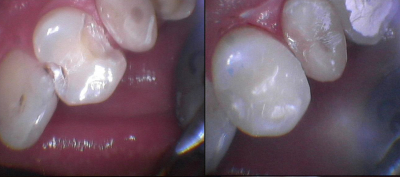

Gallery

Galeria